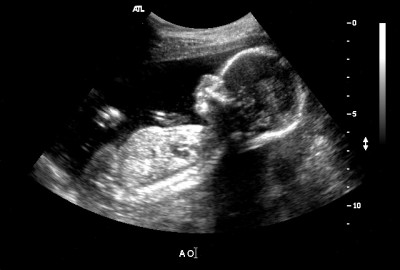

Ultragarsinės nuotraukos

Kaip atrodo pilvukai per aštuonioliktą savaitę? Visiems skirtinga. Kai kurioms motinoms atrodė, kad jos praryja kamuolį, o kitoms pilvas driekėsi iš viršaus į apačią. Viskas gerai. Kartais jie net pagal savo pilvo formą bando atspėti, ar gims mergaitė, ar berniukas.Ir vis dėlto tik ultragarso specialistas gali jums užtikrintai pasakyti, ar šią savaitę jums paskirtas toks tyrimas, ir vaikas nori pasidalyti paslaptimi.